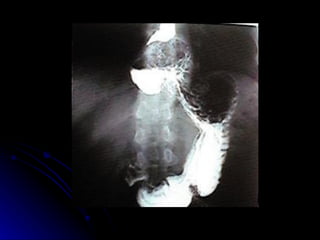

SISTEMA DIGESTÓRIO Esôfago Tubo muscular envolvido na deglutição, responsável por levar o alimento da orofaringe até o estômago 23 a 25 cm de comprimento Dividido em partes cervical, torácica e abdominal

SISTEMA DIGESTÓRIO Esôfago Inicia-se na altura da cartilagem cricóide, na projeção da 6ª VC, com trajeto descendente à frente da coluna vertebral, atravessa o mediastino superior e posterior e penetra no abdome através do hiato esofágico ao nível da 10ª VT e termina no cárdia ao nível da 11ª VT.

SISTEMA DIGESTÓRIO Esôfago  Esfíncter esofageano superior- cricofaríngeo Esfíncter esofageano inferior- espessamento camada muscular na inserção do cárdia

SISTEMA DIGESTÓRIO Possui 2 curvaturas laterais para a esquerda e 2 curvaturas no plano antero-posterior , acompanhando a coluna vertebral Possui 4 constricções EES- 15 cm Arco da Aorta- 22,5 Brônquio esquerdo- 27,5 Diafragma- 40 cm

SISTEMA DIGESTÓRIO Esôfago abdominal Cerca de 1,5 cm de comprimento após atravessar o hiato esofágico diafragmático Ligamento frenoesofágico Íntima relação com lobo hepático esquerdo Irrigação Artéria frênica inferior esquerda e ramos da gástrica esquerda Inervação  Vago e plexo simpático